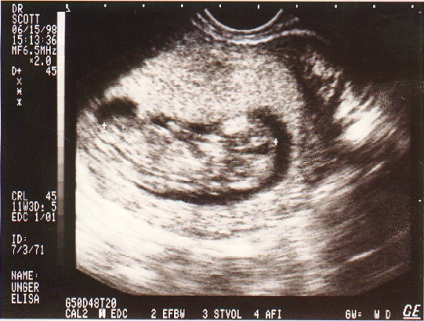

Chase @ 11 wks.jpg (130555 bytes)

11 wks u/s of Chase